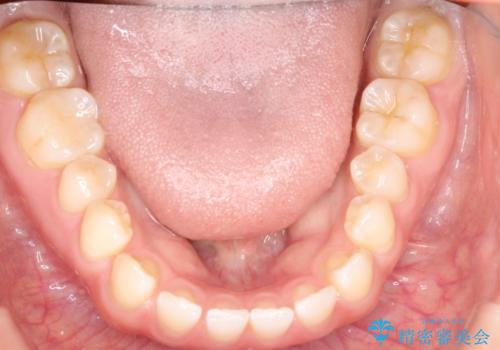

前歯の隙間を閉じたい インビザラインによる矯正

- 上下の前歯に隙間があるとのことで来院されました。

インビザラインにて隙間を閉じる矯正を行いました。

使用時間を守っていただけたので、比較的スムーズに矯正を終了することができました。